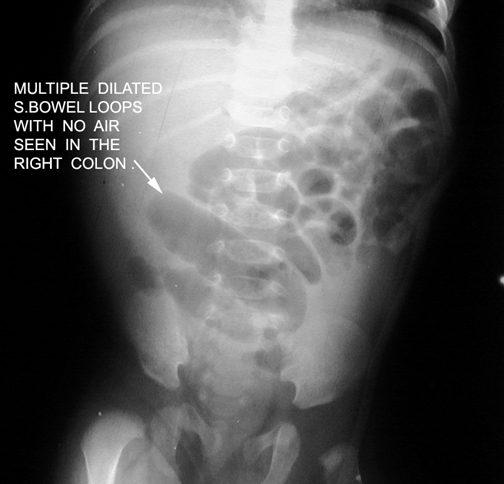

Small bowel obstruction

Absence or paucity of colon gas |